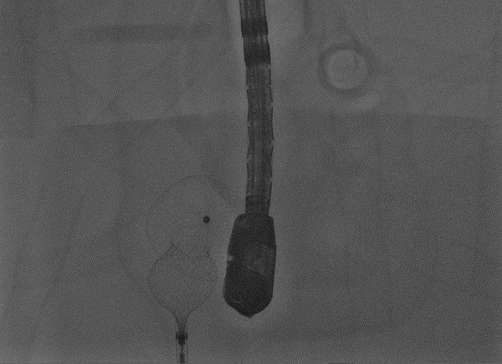

Circuit Lotusは、構造的心疾患(SHD)領域におけるASDトレーニングおよびデバイス評価のためのフローモデルとして開発されました。

初代Lotus~LotusⅡへと進化する中で確立されたのは、大型モデルによって構造全体を俯瞰し、血流下でデバイス挙動を可視化できる環境です。